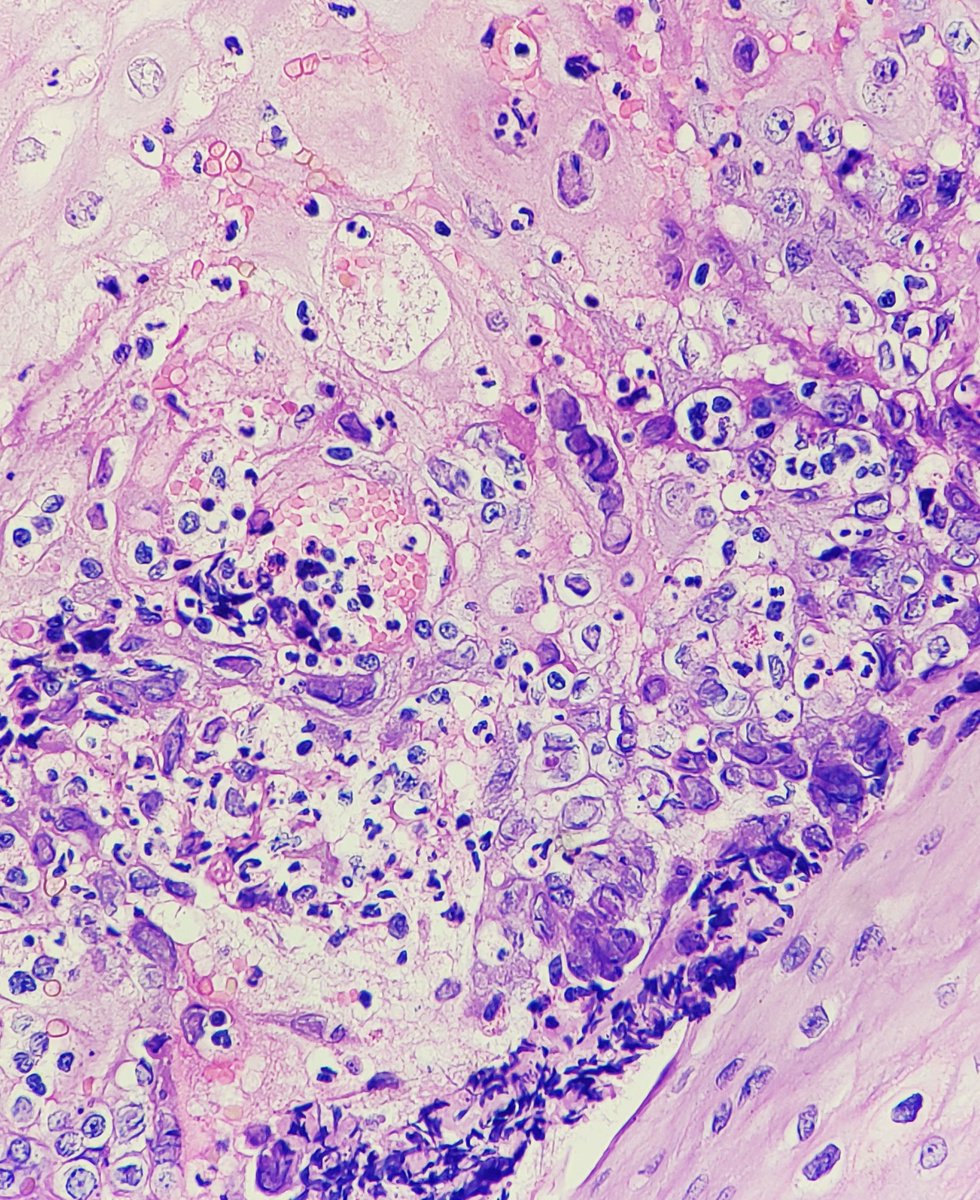

File Herpes Esophagitis Intermed Mag Jpg Libre Pathology

File Herpes Esophagitis Intermed Mag Jpg Libre Pathology from upload.wikimedia.org